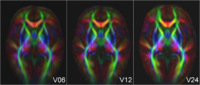

ColorFA-4D.png

Longitudinal analysis of DWI

This project develops methodology to analyze serial/longitudinal DWI data, e.g. as baseline and follow-up in trauma, serial follow-up scans as acquired in the Huntington PREDICT study, or subject-specific white matter maturation in early brain development (see picture). More...

Sharma, A., Durrleman, S. , Gilmore, J.H. , Gerig, G. Longitudinal growth modeling of discrete-time functions with application to DTI tract evolution in early neurodevelopment. Proc. of 9th IEEE International Symposium on Biomedical Imaging (ISBI May'12), p.1397-1400. N. Sadeghi, M. Prastawa, J. H. Gilmore, W. Lin, and G. Gerig, "Spatio-Temporal Analysis of Early Brain Development," in Proceedings IEEE Asilomar Conference on Signals, Systems & Computers, Nov. 2010, in print